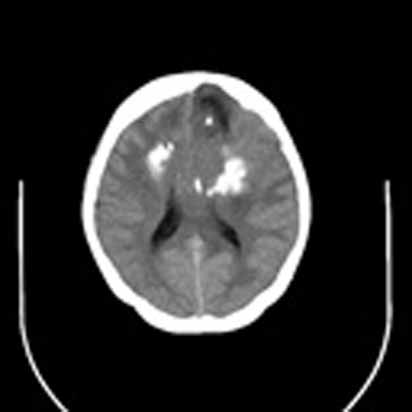

标题: CT16829:女,36,近20天偶有口眼歪斜短暂发作史,近日头痛。

近20天偶有口眼歪斜短暂发作史,近日头痛。患者先做ct发现病变后又做了mri检查,前日上传2次ct图像均未成功,今日补上。

大脑中线部位肿瘤向两侧生长,可见明显钙化影,考虑少枝胶质瘤,建议增强除外脑膜瘤

左额混杂密度肿块,经胼胝体跨越中线向右额叶生长,多考虑少支胶质细胞瘤,建议mr增强扫描,待排除血管畸形。